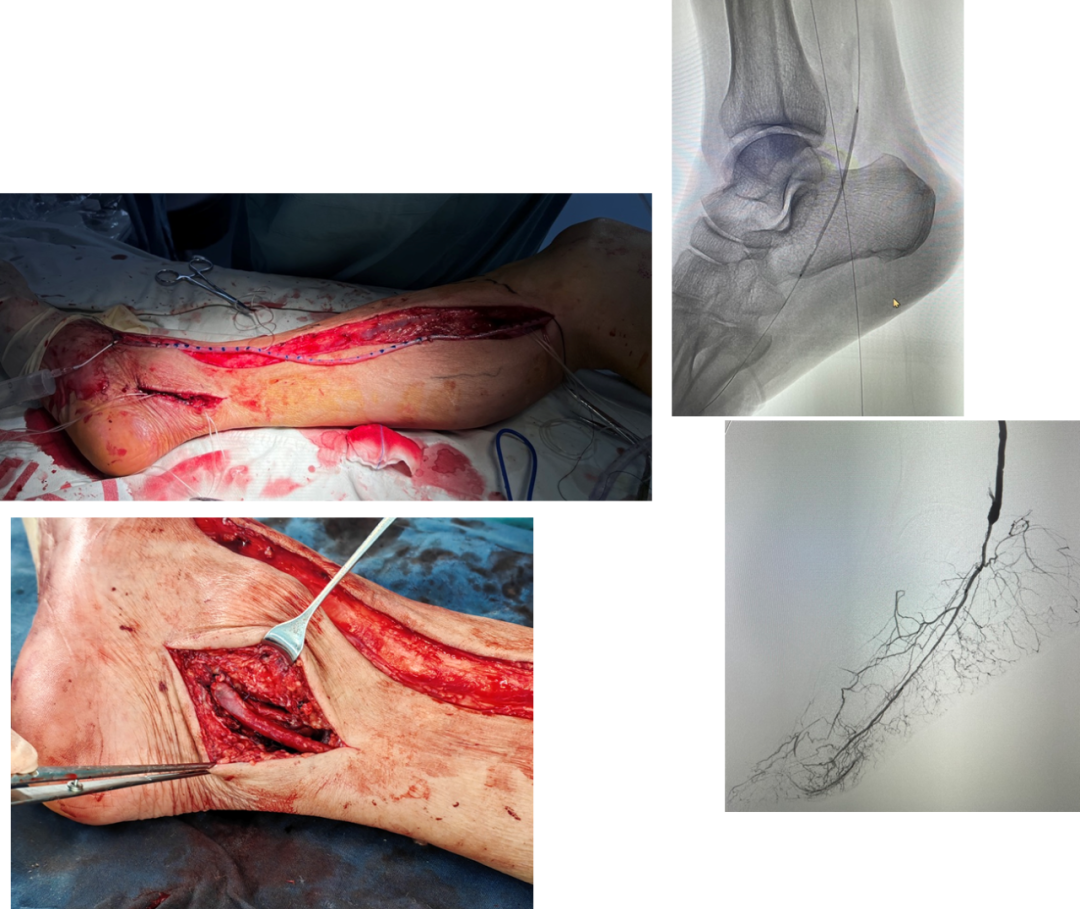

4次EVTs反复复发:R5 ischemia → 腘P3-足背non-reversed GSV旁路

EVT后临床失败:R5 ischemia → 腘P3-足底动脉 reversed GSV旁路

膝上FPAK比例不足10%,在EVT失效病例中,膝下FPBK高达38.9%

两组中,均有高比例远端旁路(踝上及踝下):57% vs 47%